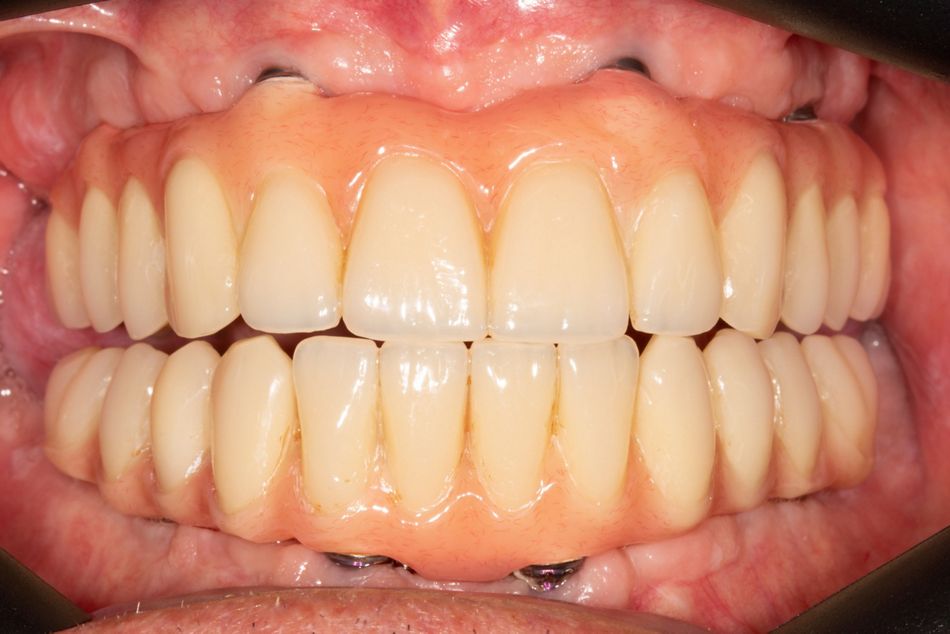

Es wurde eine erneute Abdrucknahme mit Verblockung der Abdruckpfosten vorgenommen (Pattern Resin®, GC). Nach einer Ästhetikeinprobe erfolgte die finale Versorgung mit einem individuell mit PMMA verblendeten gefrästen Gerüst (Abb. 22, 23, 24).

Der Patient bewies während der provisorischen Phase sowie im sich anschliessenden Recall ein hohes Mass an Compliance und Motivation. Die gingivalen Verhältnisse waren zu jedem Zeitpunkt reizlos (Abb. 25, 26, 27).